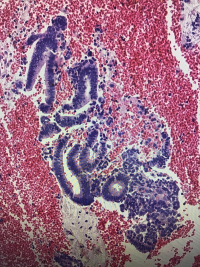

子宫内膜

性别

女

年龄

32

异常流血4天

碎组织一堆,大小2.5✖️2.0✖️0.5cm

少许破碎的增生期子宫内膜

经期内膜。